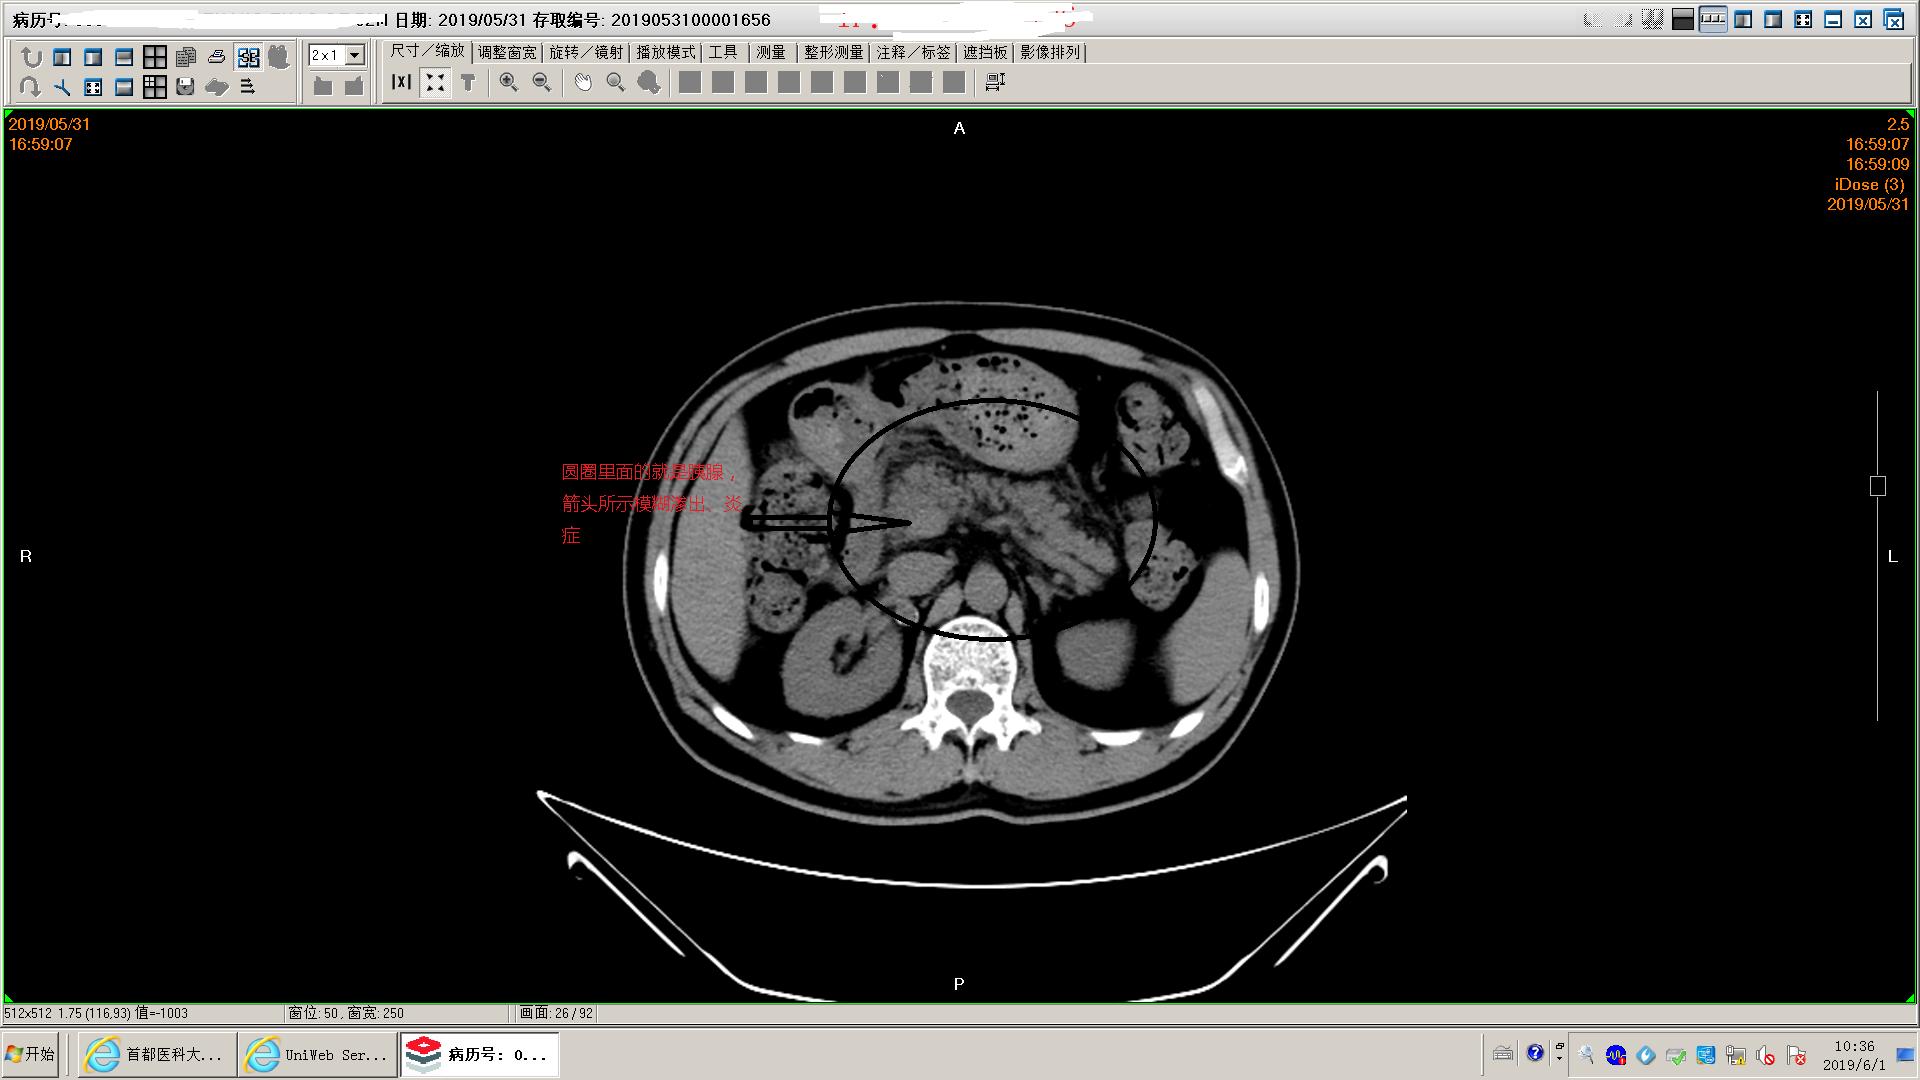

下面是一例胆源性胰腺炎影像学和化验表现,这个病人没有脏器功能不全,胰腺坏死不明显,周围没有明显积液,还不是重症胰腺炎。虽然有可疑胆管结石,但是没有黄疸,我们会在做核磁mrcp证实一下结石的位置。患者胃里面有一些残存的食物,我们会用胃管做胃肠减压,有助于胃肠道休息恢复;肠道里面积存的粪便也比较多,肠鸣音听不到,通过肥皂水灌肠促进肠道蠕动排除,有助于胃肠道功能恢复。然后给予生长抑素抑制胰酶分泌,禁食水补液,消炎治疗。

胰腺模糊渗出,坏死不明显

胰腺间隙模糊